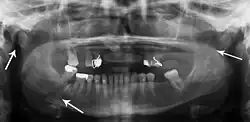

Panoramic radiograph of a simple mandible fracture of the right mandibular body, minimally displaced. Note that the teeth to the left of the fracture do not touch -

lateral oblique image demonstrating a fractured mandible.

Towne's view of a bilateral condyle fracture. White arrow is a fracture on the neck of the condyle. Black arrow shows the condyle pulled to the medial. The same injury can be seen on the opposite side -

3D CT reconstruction of mandible fracture, white arrow marks fracture, red arrow marks moderate displacement and open bite -

occlusal radiograph of a mandibular parasymphysis fracture